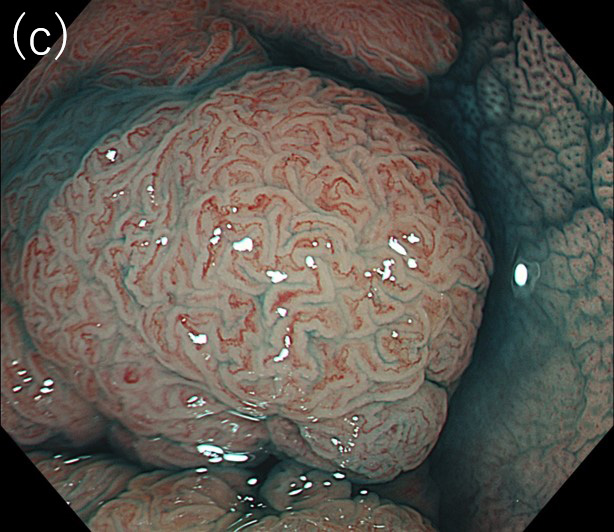

〈図3〉 XZ1200による30mm大Is+IIa(LST-G)病変

(病理診断:Adenocarcinoma, tub1, in tubular adenoma, pTis, Ly0, V0)に対する観察像

(a)白色光中遠景観察像

(b)NBI拡大観察像(JNET分類:Type 2A)

(c)インジゴカルミン散布後の拡大観察像

(d)クリスタルバイオレット染色後の拡大観察像(pit pattern:Ⅳ)